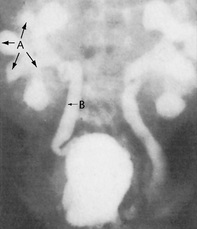

Computed tomography (CT) is a quick and non-invasive technique, which can be used with or without contrast. It is used to define renal and retroperitoneal masses and is ideal for locating and staging renal tumours (Fig. 8.20). It is also used to show polycystic kidney disease and has the advantage of also highlighting non-renal pathology. Modern techniques involving spiral CT can be used to visualize the anatomy of the renal arteries, renal vein and inferior vena cava, as well as retroperitoneal studies. Increasingly, CT without contrast is the investigation of choice to diagnose obstruction to the urinary tract or renal calculi (Fig. 8.21).

image

Fig. 8.21 An abdominal CT scan of a patient who presented with acute renal failure and bilateral loin pain. There is bilateral hydronephrosis secondary to bilateral ureteric stones. In the upper image a nephrostomy tube is seen in the right renal pelvis (A). The lower image demonstrates a dense opacity (calculus) lying in the ureter approximately at the level of L2 (B). Subsequent images demonstrated a similar opacity at L3 on the left.